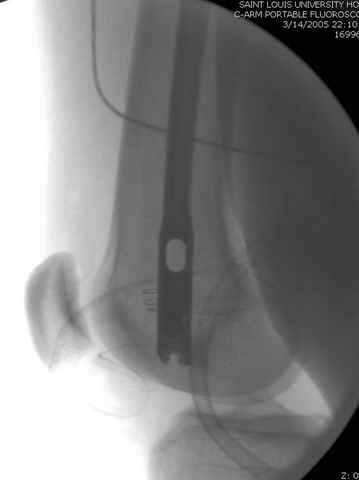

По поводу открытого перелома больной ургентно взят на ретроградное интрамедулярное штифтование, после рутинного дебрайдмента и фасциотомии на бедре и на голени.

перелом бедра

интраоперационные

|